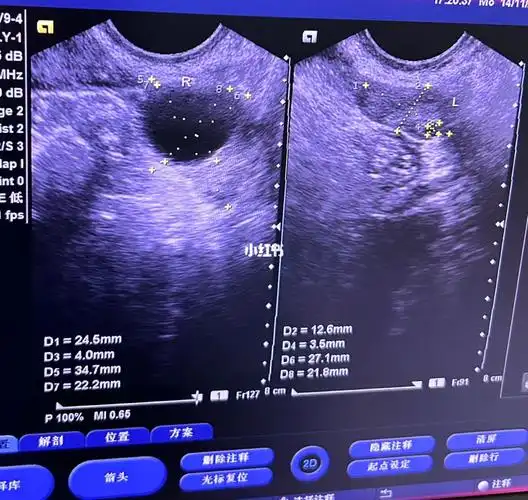

月经第17天卵泡监测2221